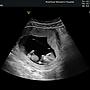

126F→: 要看性別問醫生阿 要拍兩腳開開的角度才看的到01/04 16:27